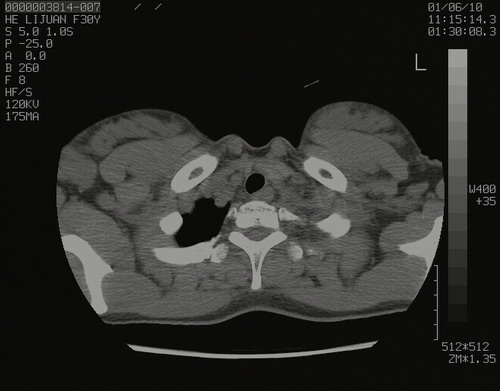

怀孕3个月时(2009-3至4月间),自述突感左侧前后胸疼痛1天,以前胸明显,随后偶感闷痛,余未见异

左肺尖脊柱旁沟肿块,境界清楚,边缘光滑,密度不均,内有多发点片状钙化,考虑良性肿瘤,骨软骨瘤或神经源性肿瘤可能,肺错构瘤不除外。

左后上纵隔见一类圆形肿块影,外侧边界清,密度不均匀,内可见点状钙化影,增强呈不均匀强化,考虑神经源性肿瘤可能。期待病理结果。